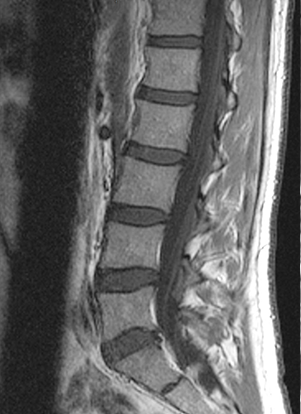

坐骨神経痛に限らず、痛みや身体の不調があると病院に行って検査を受けるのが当たり前のことだと思います。それは病気や身体の専門家としてお医者さんは国家資格として認められた職業だからです。その中でも坐骨神経痛のように脚の痛みやしびれなどがある場合は整形外科を受診することが通常です。整形外科に行くとまず初めにレントゲンで腰椎(腰の背骨)を撮影し骨に異常が無いかを確認します。そして次にMRIを行って脊髄の流れに異常がないか、椎間板が膨隆・突出して脊髄を圧迫していないかを確認します。

このような場合は椎間板ヘルニアと診断されるでしょう。飛び出した椎間板が脊髄を圧迫しています。

この場合はどうでしょうか?一番下とその上の椎間板が少し形が変わっていますが、脊髄の圧迫はありません。

この2枚のMRI画像のように全く違う状態なのに症状はほとんど変わらないということも良くあるのですが、整形外科ではもうどっちがどう違うのか全く分からなくなっていて病院によっても言うことが全然違うなんてことも少なくありません。